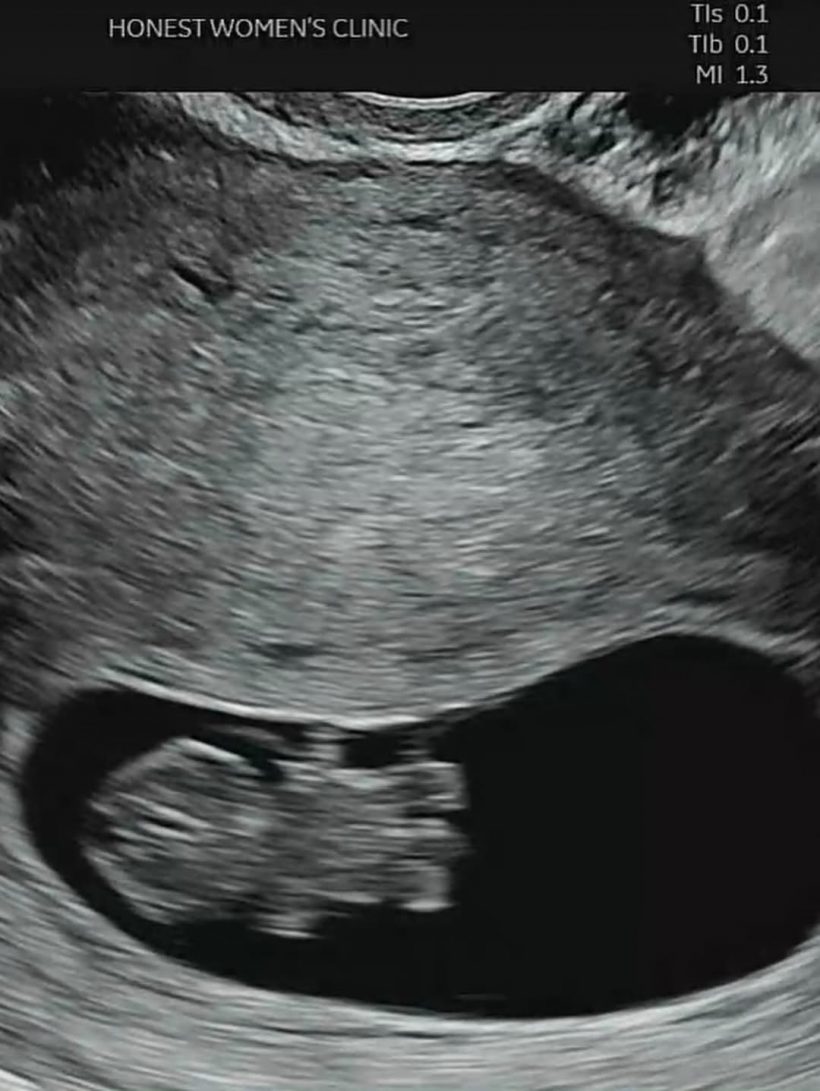

เธอได้โพสต์ภาพปาร์ตี้ประกาศข่าวท้อง และภาพอัลตราซาวนด์ให้แฟน ๆ ได้ร่วมยินดี ซึ่งก็ได้รับคอมเมนต์อวยพรล้นหลาม